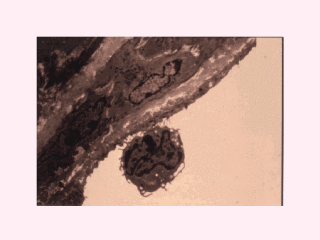

急性期细胞因子有什么作用?这张幻灯片展示了细胞因子对内皮细胞的激活效果。内皮细胞被肿瘤坏死因子α,白介素1,白介素6激活后表达一系列粘附分子,后者致使淋巴细胞的翻滚和粘附,这可能是动脉粥样硬化病灶中脂类条带形成的最早时相。